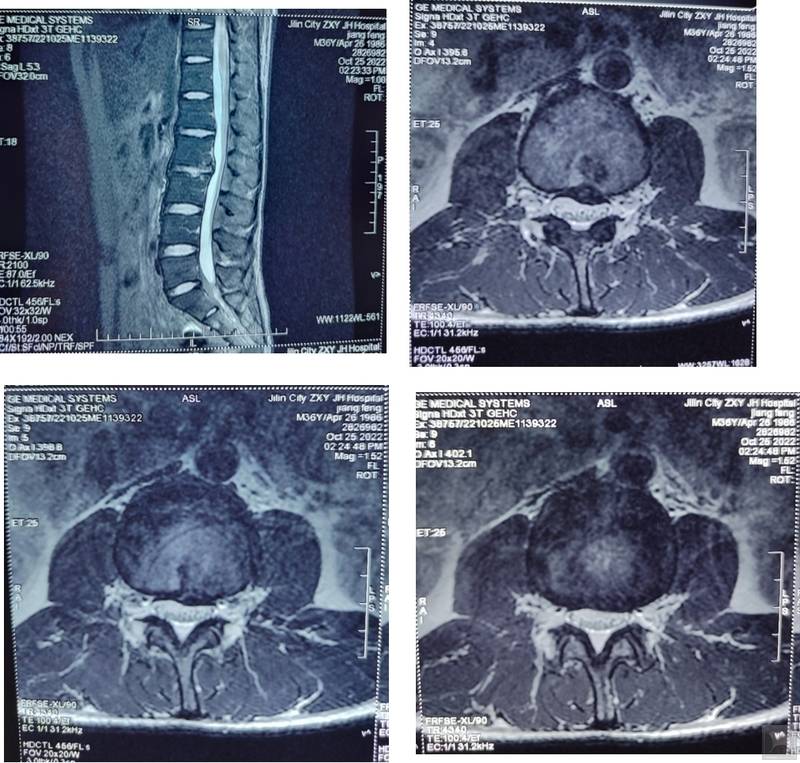

患者主诉“腰痛伴左下肢放射痛2天”。患者于2天前患者在家抬举重物时腰部出现弹响,而后出现腰痛伴左下肢放射痛,卧床休息后未改善,于本院查腰椎MRI示(如图): L2~L3椎间盘向左后方脱出,左侧神经根受压。就诊时症见:患者腰骶部疼痛,弯腰活动受限,左下肢放射痛,疼痛区集中在大腿前侧,纳眠可,二便调,舌淡红,苔白,脉细。

随访:该患者于2022年10月25日在我院体检,腰椎MRI(如图)示: L2~L3椎间盘膨出。患者症状消失。